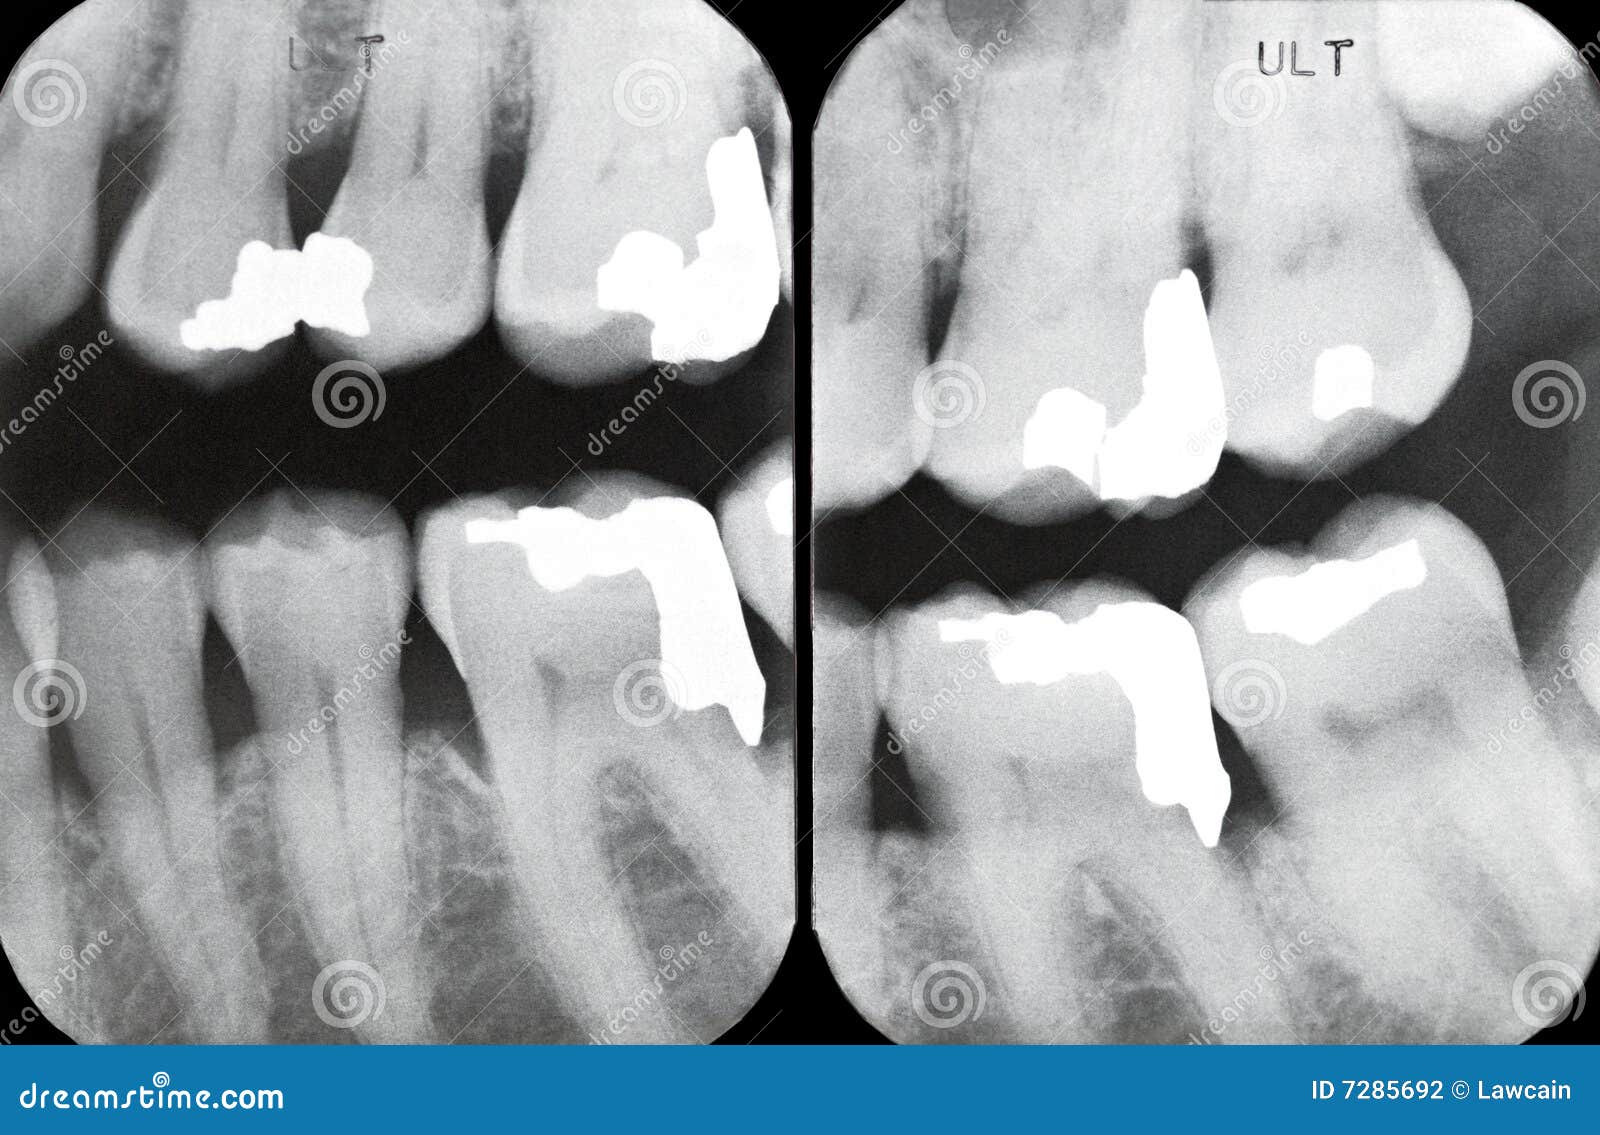

From dreamstime.com

Right Periodontal Xrays Stock Photography Image 7285692 Periodontal X Ray The optimal projections for periodontal diagnosis in the posterior teeth are bitewing radiographs if. the use of the periodontal probe in the periodontal pockets around teeth provides information on pocket depth,. an opg provides us a complete bilateral view of dentition, maxilla, mandible and temporomandibular joint (tmj). it is generally widely accepted that radiographs supplement clinical examination. Periodontal X Ray.